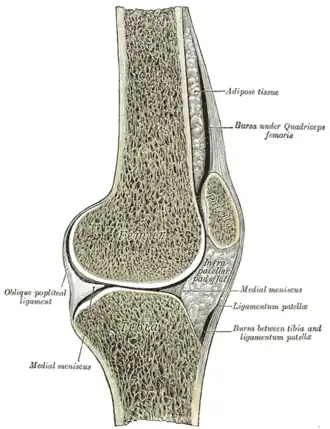

En los miembros superiores normalmente se hallan en la articulación de la cara palmar de la mano. Los dos más comunes están en los tendones de las dos porciones del flexor corto del pulgar, en la articulación metacarpofalángica. En los miembros inferiores el sesamoideo de mayor tamaño es la rótula. Otro sesamoideo situado en la parte posterior de la rodilla es la fabela, localizado en el espesor del tendón del gemelo externo, y que en ocasiones puede confundirse con un cuerpo libre interarticular. Los huesos sesamoideos, además de en las articulaciones, pueden hallarse en los tendones del miembro superior, o a veces en el tendón del bíceps braquial, también se observan en los tendones de las extremidades superiores. En algunas situaciones se produce inflamación a nivel de los hacecillos, principalmente en la base del dedo gordo, produciéndose una sesamoiditis.

- Articulación rodilla cara posterior (fabella)